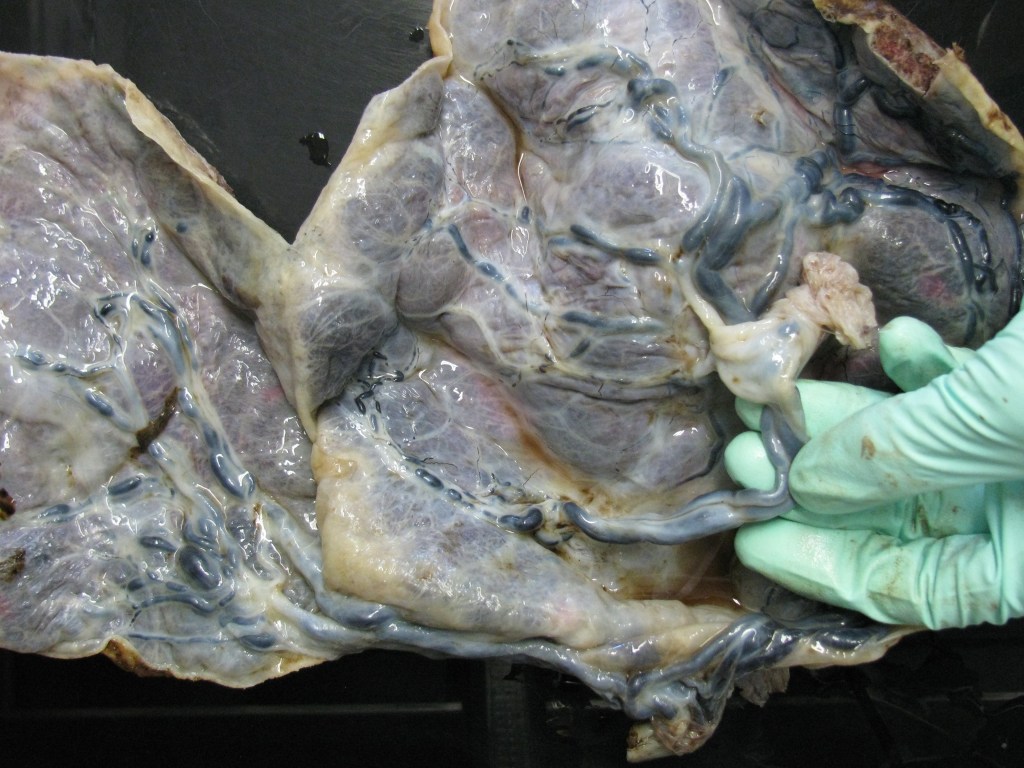

- Insertion of the umbilical cord: the umbilical cord is usually inserted centrally or eccentrically. Other sites of umbilical cord insertion include marginal insertion, marginal insertion with velamentous vessels, furcate insertion, interpositional insertion(cord inserts into membranes but does not lose Wharton’s jelly), and velamentous insertions. Insertions should be clearly noted on gross description. Eccentric and marginal insertions will not likely have a huge impact on a baby; however velamentous and furcate insertions may have consequences. About 1% of the cord’s insertion will be a velamentous or membranous insertion, which means that umbilical cord vessels will run freely in the membranes, and they lack Wharton’s jelly. This can lead to trauma at the time of delivery, nicking, and subsequently, thrombotic lesions.

- Cross-section of the umbilical cord usually reveals three (3) blood vessels (two umbilical arteries and one umbilical vein). If only two vessels are noted then the finding of the single umbilical artery should always be documented closer to the fetal end of the cord. Umbilical arteries tend to have anastomoses (Hyrtl’s anastomoses) and they tend to fuse little bit closer to the fetal end. The other finding that can be grossly examined is the presence or absence of thrombotic lesions in the umbilical vessels. The thrombotic lesions present as little white-tan plugs in the umbilical vessels. It is very important to document these. Presence of thrombosis in the umbilical cord is associated with fetal thrombotic lesions and with intrauterine fetal demise and intrauterine fetal growth restriction.